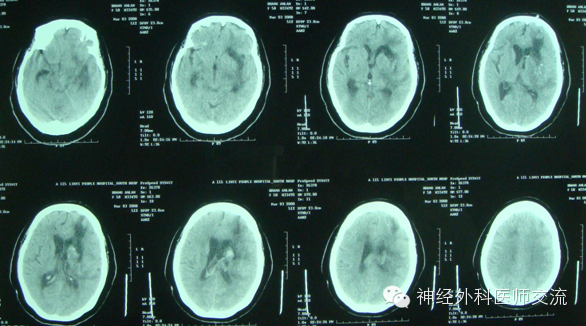

很普通的病例,术后4小时,突发脑疝,静推1瓶甘露醇,急查CT

从三通侧臂,抽不出血来。拔除引流导管,按照新的CT,从原骨孔重新置管,从新操作

远端的血清掉后,回撤导管,再液化引流

原因:术后病人烦躁、血压恶性升高,致再出血,导成血肿扩大。